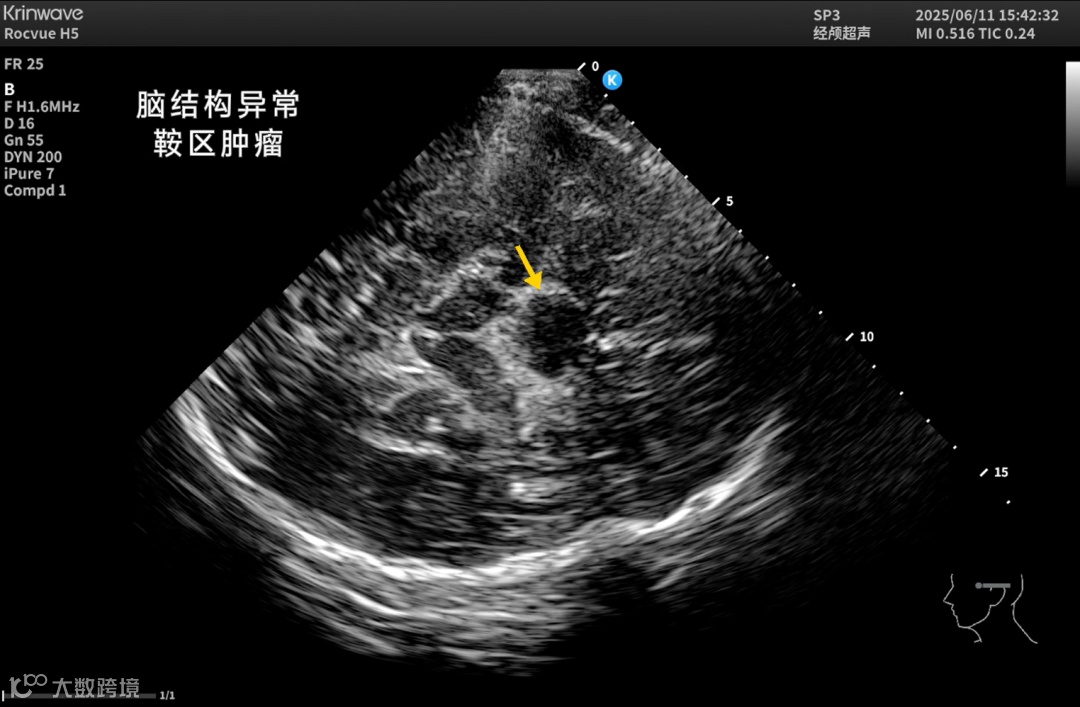

凭借更强的穿透力、更高的帧率和更清晰的组织呈现,鲲为颅脑超声能提供优质的颅内二维影像和血流影像,在更多临床与科研场景中具备可被依赖的影像表现:

在本次 RSNA 展台,影像科医师们被设备实时呈现的颅内影像吸引而驻足,亲自上手实操感受鲲为超声穿透颅骨的实时影像表现,清晰的脑室结构更是前所未有的视野。

也正因为这份突破,Rocvue H系列超高端科研超声在神经重症、脑出血监测、帕金森诊断、儿科管理、神外术中评估、颈脑一体化观察,以及神经系统疾病科研等场景中,都展示出颅脑超声更多可被依赖的未来图景。